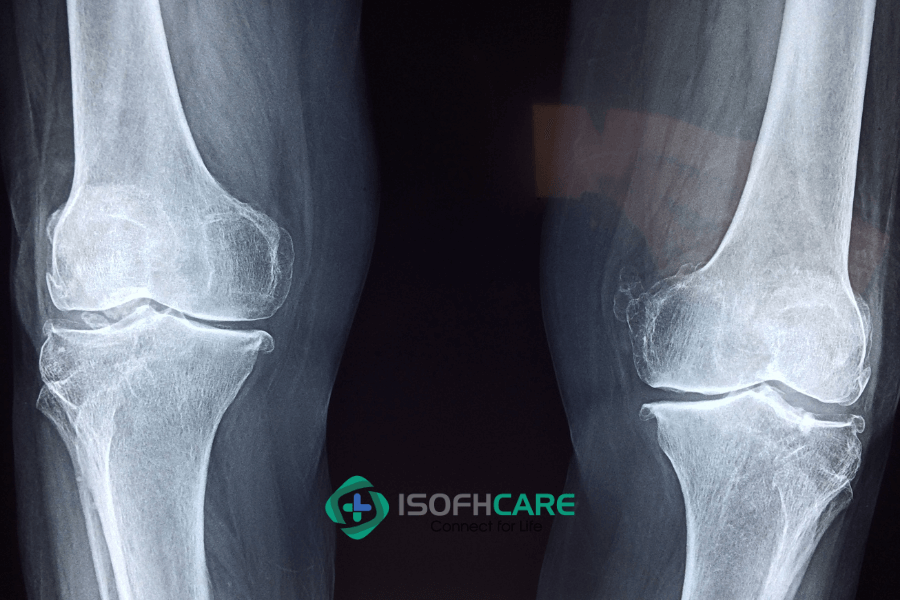

a. Chụp Xquang

Chụp Xquang là xét nghiệm hình ảnh đưa ra kết quả phim về cấu trúc xương, vị trí khối u cơ thể. Dựa vào hình ảnh trên phim Xquang, bác sĩ sẽ đưa ra phán đoán vị trí đau, bất thường có liên quan đến khối u ung thư xương hay không.